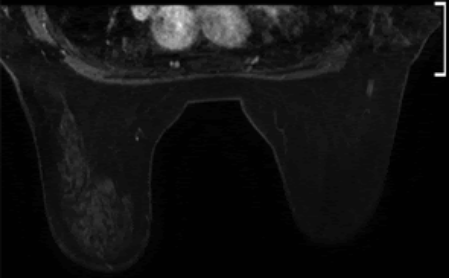

5. Đặc điểm hình ảnh và phương tiện khảo sát

Hầu hết tuyến vú được tìm thấy ngẫu nhiên trên chụp nhũ ảnh thường quy. Hình ảnh siêu âm cho thấy mô vú, không thể phân biệt với mô vú thông thường. Đôi khi, chụp cộng hưởng từ tuyến vú được thực hiện trong các trường hợp không điển hình. Biểu hiện bằng các đặc tính tín hiệu và ngấm thuốc tương tự như mô tuyến bình thường.